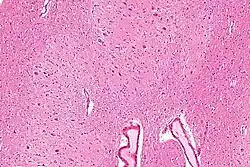

![]() Sección sagital por el hemisferio derecho cerebelar. La oliva derecha, "el núcleo olivar inferior" se ha cortado en el plano sagital — de frente hacia atrás. (Núcleo dentado, "nucleus dentatus" marcado arriba.